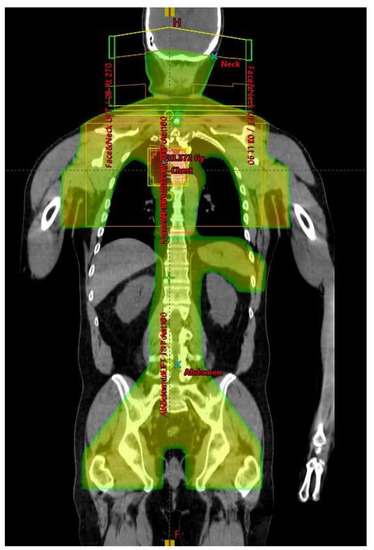

4.4. Radiotherapy

4.5. Supradiapragmatic RT

4.6. Infradiaphragmatic RT